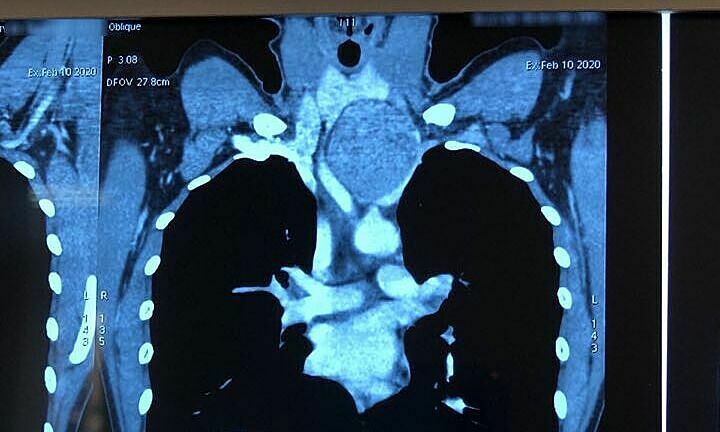

Trong kiểm tra sơ bộ, bác sĩ nghi ngờ bệnh nhân đã để lại khối u tuyến giáp. Bệnh nhân được chụp cắt lớp 64 giờ và sinh thiết bằng kim. Kết quả chẩn đoán hình ảnh và chẩn đoán được xác định là khối u tuyến ức loại AB của trung thất trước và phần cổ trái. Khối u dài 8x5cm và còn được gọi là tuyến ức ngoài tử cung.

Ngoại trừ phẫu thuật tuyến ức thông thường, điều này không được thực hiện thông qua phẫu thuật ngực, mà thông qua một vết mổ ở cổ. Sau ca phẫu thuật, bệnh nhân đã hồi phục nhanh chóng và được xuất viện 3 ngày sau đó – một màng khối u lớn bao phủ cổ. Ảnh: Vũ Hương.